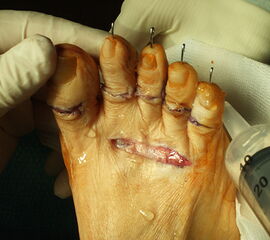

Dorsaler Zugang zur Resektionsarthroplastik der Mittelfußköpfchen 2-5.

Abbildung 9

Nach der Hautinzision erfolgt die Darstellung der Strecksehnen. Die kurzen Strecksehnen werden tenotomiert. Dann wird die Gelenkkapsel des MTP-Gelenkes dorsal eröffnet und das Gelenk gründlich synovektomiert. Der kontrakte Seitenbandapparat wird scharf abgelöst. Das Metatarsaleköpfchen wird nun dargestellt und mit einer oszillierenden Säge möglichst sparsam von distal-dorsal nach proximal-plantar reseziert. Wichtig ist hierbei ein harmonisches Alignement der Metatarsalia zu erreichen. In Neutralstellung des oberen Sprunggelenkes wird nun getestet, ob sich die MTP-Gelenke neutral einstellen, sonst muss evtl. eine z-förmige Verlängerung der langen Strecksehnen angeschlossen werden, bei kontrakten PIP-Gelenken möglicherweise auch eine Arthrodese der PIP-Gelenke mit temporärer K-Drahtschienung.